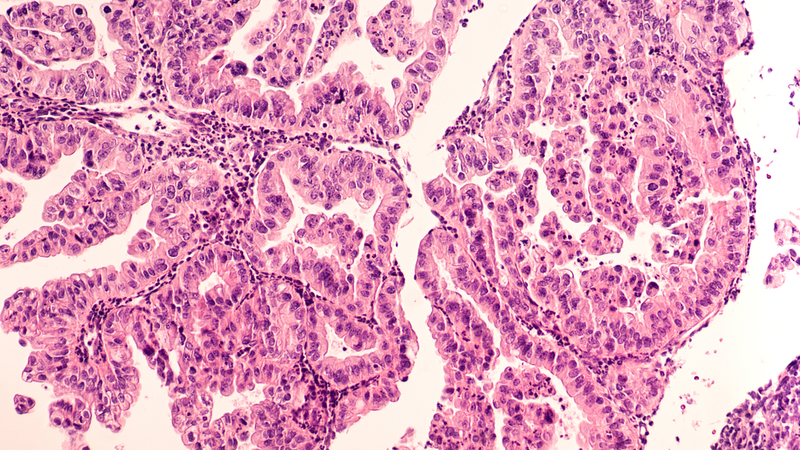

One head of this dual pronged "arrow" strikes what is known as the death receptor on the cancer cells, forcing them to die, while the other head strikes a receptor known as FOLR1, a well established marker that suggests a poor prognosis. "There are a lot of efforts in terms of cancer immune therapy, but the success of these are really limited in solid tumours," Tushir-Singh said.

"I found that one of the problems is with the solid tumour microenvironment. "The microenvironment is highly hypoxic, anergic and, particularly in the case of ovarian cancer, some unusually large receptors form a protective fence around tumour cells, so even if the immune cells reach there, there are many obstacles," he explained.